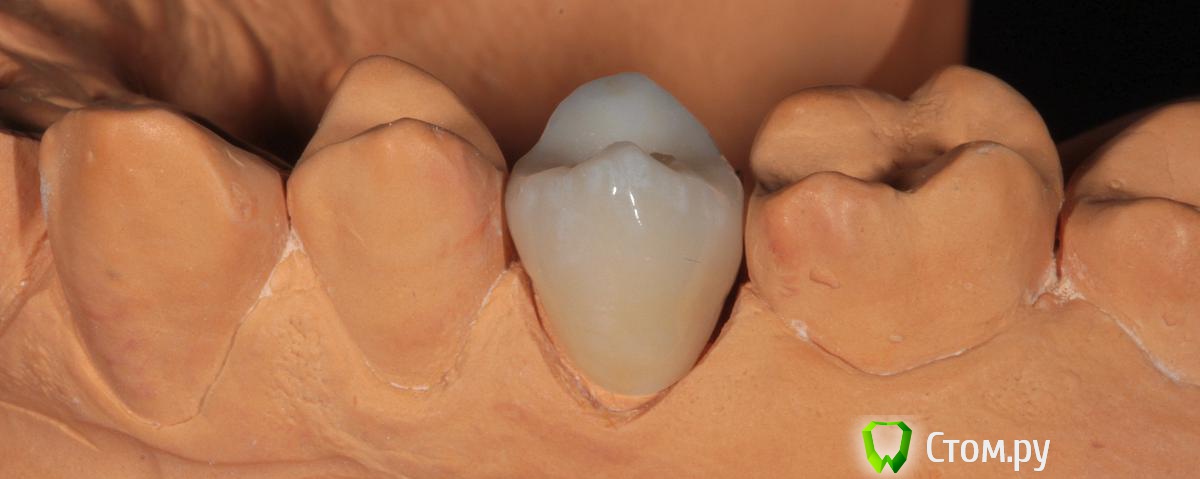

SDC Опубликовано 19 ноября, 2014 Поделиться Опубликовано 19 ноября, 2014 (изменено) Prettau, извините, не знаю, как редактировать название темы. Здравствуйте всем. В хирургическом много практиков, а по протетике - много теории)). Итак, разбавляю вино. (теория вечна)Протезирование премоляров коронками Преттау с нанесением керамики вестибулярно.Много фото, прошу прощения, поэтому без радикала, превью. Наверное даже так лучше, потому, что по клику откроются не сжатые фото, а радикал жмет.Протезирование в течение 2 недель. Фиксация на фуджи, без коффердама, но в сухих условиях (коффер не поставить по причине глубокий дистальной границы препарирования на обоих премолярах - глубокий кариес проксимальных поверхностей в анамнезе)Рг-контроль на предмет остатков цемента и на последнем фото удаленные излишки цемента на перчатке. Изменено 19 ноября, 2014 пользователем SDC 7 Ссылка на комментарий

SDC Опубликовано 20 ноября, 2014 Автор Поделиться Опубликовано 20 ноября, 2014 Отличный результат. Позвольте несколько вопросов.СВШ в боковых не ставите вообще,если да,то по какой причине?Как думаете антагонисты не будут истираться?Вы как-то меняете анатомию контакта при глубоких дефектах и недостатка сосочка?Спасибо.Спасибо Роман.По поводу штифтов. На самом деле, не имеет значения для меня.Важно, что не было титановых во фронтальном отделе (открываются при редукции тв.тк. небольшой объем композита вокруг штифта, что приводит к хрупкости билдапа и иногда металл.штифты светят через композит и керамику)Антагонисты истираться будут, а цирконий - нет. Что поделаешь.Сейчас мы с техником делаем нанесение вестибулярно и по скатам бугров, для уменьшения негативного эффекта повышенной прочности циркония и ускорения сдаваемости.контакт всегда площадочный, пятно контакта в корональной 1/4.Дефицит мягких тканей керамикой никогда не восполняем. Моделировка коронки максимально анатомична. Ссылка на комментарий